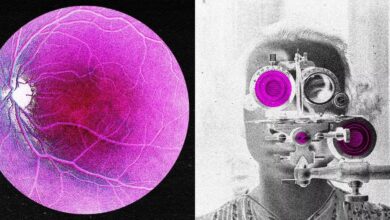

پزشکان و محققان درگیر یک مسئله مهم در مورد ریتم قلب هستند: چرا زنان ضربان قلب سریع تری دارند ، در حالی که مردان به احتمال زیاد ریتم های نامنظم مانند فیبریلاسیون دهلیزی (AFIB) دارند؟ محققان دانشگاه ایالتی اوهایو اکنون در یک مطالعه جدید جواب داده اند.

براساس گزارش Sciencheedy ، محققان دریافتند که گره گناهکار یا سان (یک ساختار کوچک اما قدرتمند در قلب انسان که باعث شروع هرگونه ضربان قلب طبیعی می شود) در مردان و زنان بر اساس ژنتیک خود. به عبارت دیگر ، زنان ژنهایی دارند که ضربان قلب خود را سریعتر می کند ، از یک طرف ژنهایی در مردان وجود دارد که می تواند منجر به مشکلات قلبی مانند فیبریلاسیون دهلیزی شود.

محققان در مطالعه حاضر قلبهای اهدای انسانی را برای تجزیه و تحلیل ژن ها در سلولهای منبر SAN مسئول تولید و نگهداری ضربان قلب مورد بررسی قرار دادند. دریافت که زنان سطح بالاتری از TBX3 و HCN1 دارند. 2 ژن کلیدی که باعث ریتم سریعتر قلب می شوند. در مقابل ، قلب مردان در شبکه های ژن مرتبط با التهاب و تولید کلاژن فعال تر بودند ، که می تواند در سیگنال های الکتریکی تداخل داشته و خطر آریتمی را افزایش دهد.